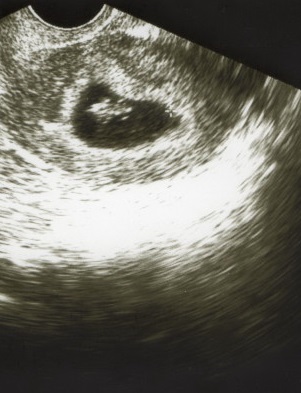

Наша бусинка в 7+1 недель

УЗИ, КТГ, доплерВот она, наша бусинка, наша маленькая трепыхающаяся точечка

Бусинкины размерчики:

КТР - 10 мм

Желточный мешочек - 4,7 мм

Плодное яйцо - 34*38*11

СБ - 150 уд/мин